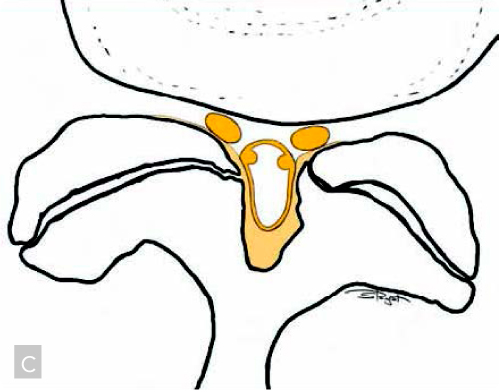

Sia il canale vertebrale che ospita il midollo spinale e la cauda equina, sia i forami di coniugazione dai quali passano le radici spinali, durante l’invecchiamento vanno incontro ad una riduzione di volume a causa della riduzione di altezza del disco intervertebrale, della presenza di frammenti di nucleo polposo erniato, di osteofiti delle apofisi articolari (c). Queste alterazioni avvengono di norma molto lentamente, pertanto, le strutture nervose in genere si adattano e trovano un loro spazio. La colonna artrosica dell’anziano può essere anche del tutto asintomatica.